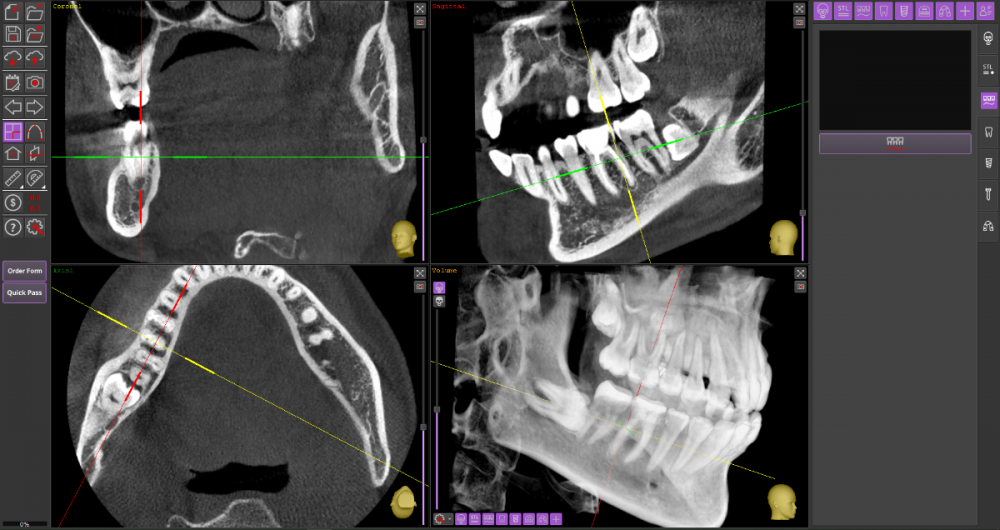

Прошу Вашего совета по поводу удаления восьмых зубов.

Из жалоб есть непродолжительная ноющая боль в правой нижней челюсти, не связанная с внешними раздражителями.

1. Необходимо ли удаление зубов мудрости?

2. Возможно ли удаление амбулаторно, без общего наркоза?

3. Нет ли риска для семёрок при удалении.

DICOM во вложении на Яндекс.Диске https://disk.yandex.ru/d/mBS1B4TYMHIf1A

Виновником боли в н.ч. справа может быть, например зуб 46, не только 48.

1. Удаление 8-х зубов скорее всего необходимо

2. Удаление амбулаторно вполне возможно. Общая анестезия (наркоз) совершенно необязательна, местной анестезии достаточно.

3. Несчастные случаи бывают, но крайне редко.